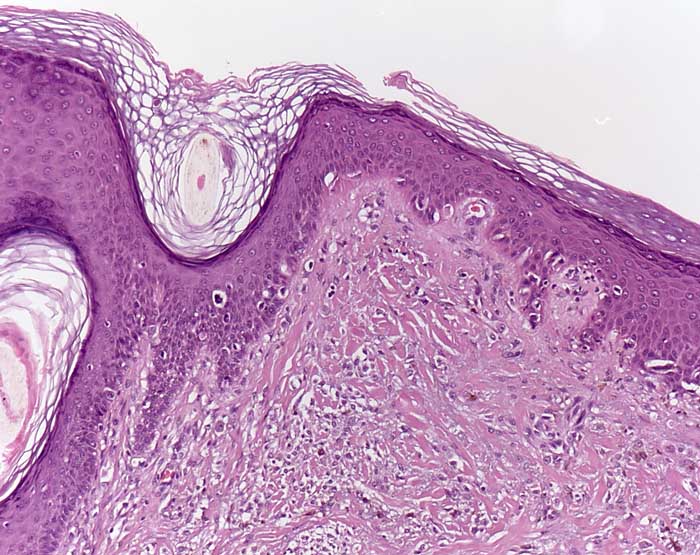

PathoPic – image database / PathoPic ID 7757 - Desmoplastisches Melanom (Lentigo maligna Melanom)

Desmoplastisches Melanom (Lentigo maligna Melanom)

maligner Tumor

Haut, Kopf

Haut

Lentiginöse Hyperplasie atypischer Melanozyten entlang der Junktionszone entsprechend einer Lentigo maligna. Die angrenzende Dermis ist narbenartig fibrosiert und ist auffallend zellreich (desmoplastisches Melanom). Die dermalen Zellen weisen lediglich geringe Atypien auf.

Histologie

100